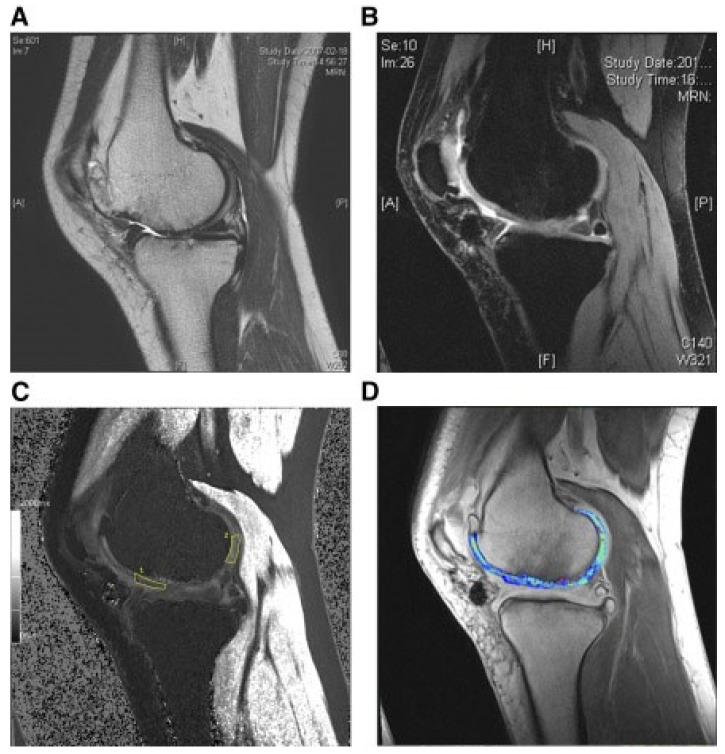

還評估了人臍帶血來源的間充質(zhì)干細(xì)胞(HUCB-MSC)治療軟骨再生的安全性和有效性。根據(jù)國際軟骨修復(fù)協(xié)會(huì)的數(shù)據(jù),HUCB-MSC用于治療7名患有KLIII級OA和IV級軟骨缺損的患者。同種異體HUCB-MSC在體外生長,然后與HA水凝膠結(jié)合并應(yīng)用于損傷部位。微骨折方案與這些細(xì)胞結(jié)合使用。12周后,修復(fù)的組織似乎成熟,24周后,臨床評分增加。在整個(gè)7年隨訪過程中,臨床改善的穩(wěn)定性也值得注意。組織學(xué)用于在手術(shù)后一年顯示透明軟骨,而MRI用于在手術(shù)后3年顯示軟骨再生,如圖所示圖3(其中釓-DTPA用作造影劑,以藍(lán)色顯示)。

(A) 術(shù)前軟骨缺損。(B) 移植后3年軟骨再生。(C) 通過在標(biāo)記區(qū)域采樣來計(jì)算相對軟骨松弛率的變化。(D) 顯示與藍(lán)色信號相關(guān)的GAG含量增加。